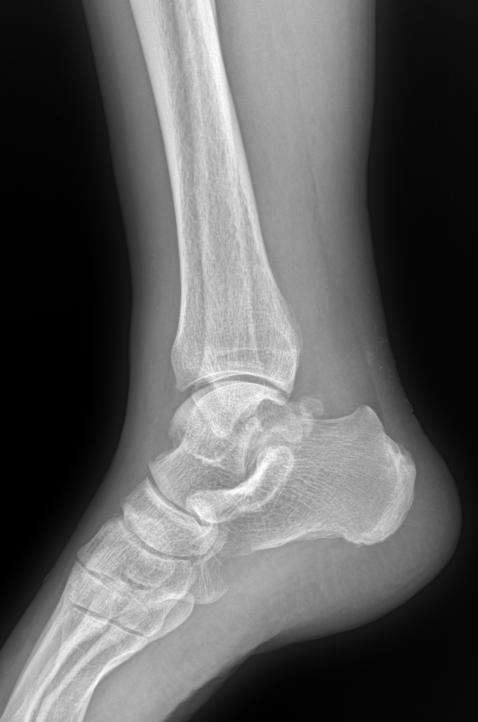

男 71 外伤疼痛20天 软组织肿胀